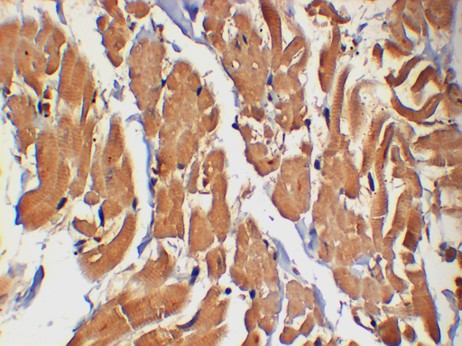

P38 Monoclonal Antibody (2F12)

P38 Monoclonal Antibody (2F12)

P38 Mouse Monoclonal Antibody (2F12). Isotype: IgG1. Species Reactivity: Human, Mouse, Rat. Source: Mouse. Antigen: Recombinant Protein. Composition and storage: 1 mg/mL in PBS, pH 7.4, containing 0.02% sodium azide and 50% glycerol. Store at -20C. Stable for one year from the date of shipment.

IHC

IHC 1:1,000-2,000